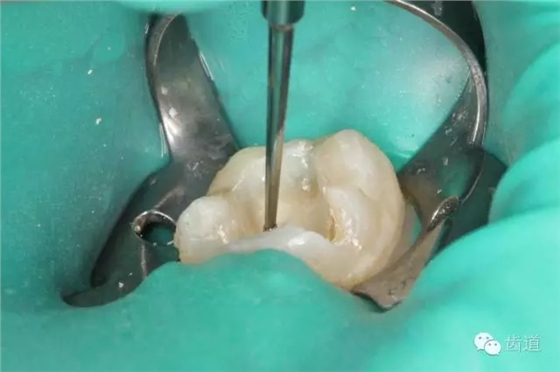

4. 初步開(kāi)髓

5. Endo-Z揭全髓室頂

6. 可見(jiàn)髓腔內(nèi)壞死牙髓組織,無(wú)滲出

7. 3%次氯酸鈉浸泡髓腔5min

8. 浸泡后超聲清理髓腔,去除髓腔內(nèi)殘留牙髓組織